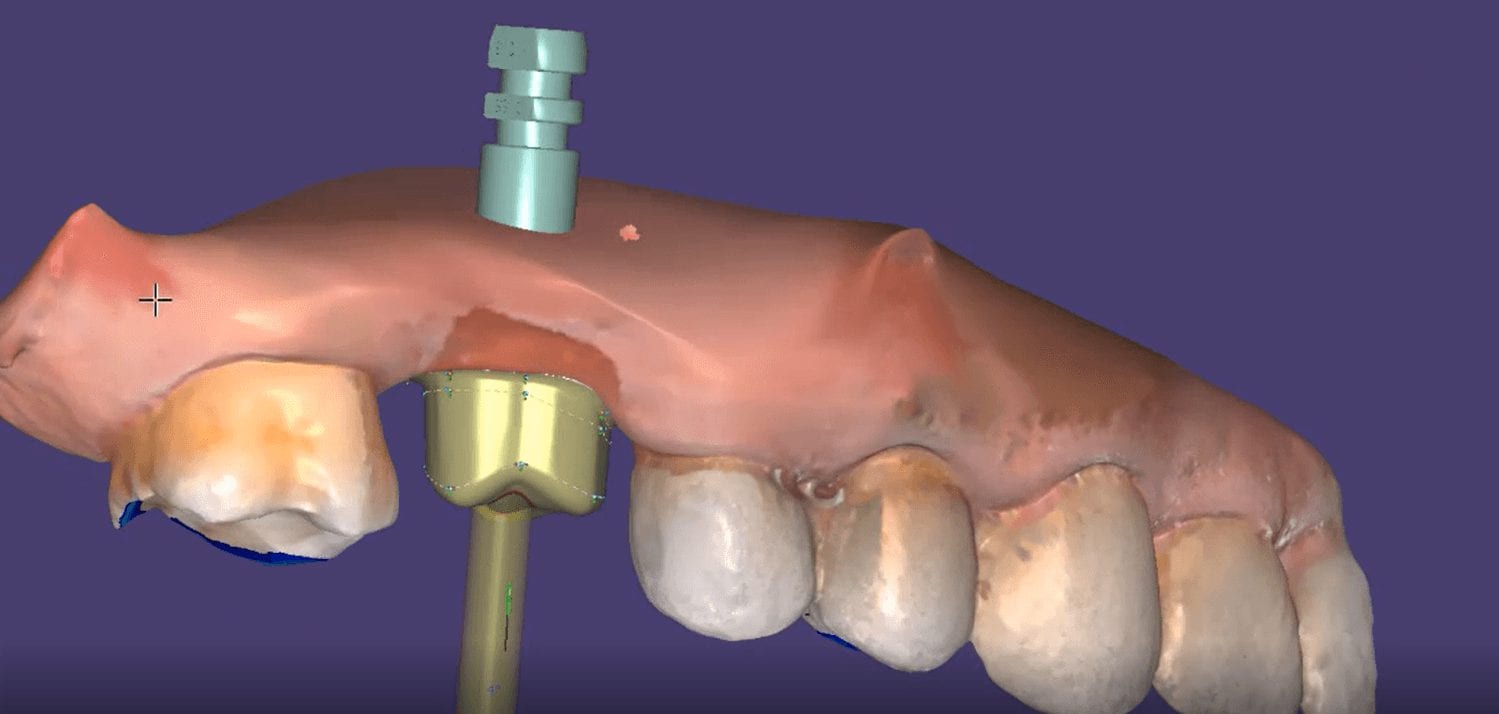

May 29, 2019A friendly reminder- this case was table top scanned with a desktop scanner so don’t get distracted, but be aware that for oral appliances, particularly for apnea treatment or bruxism, […]